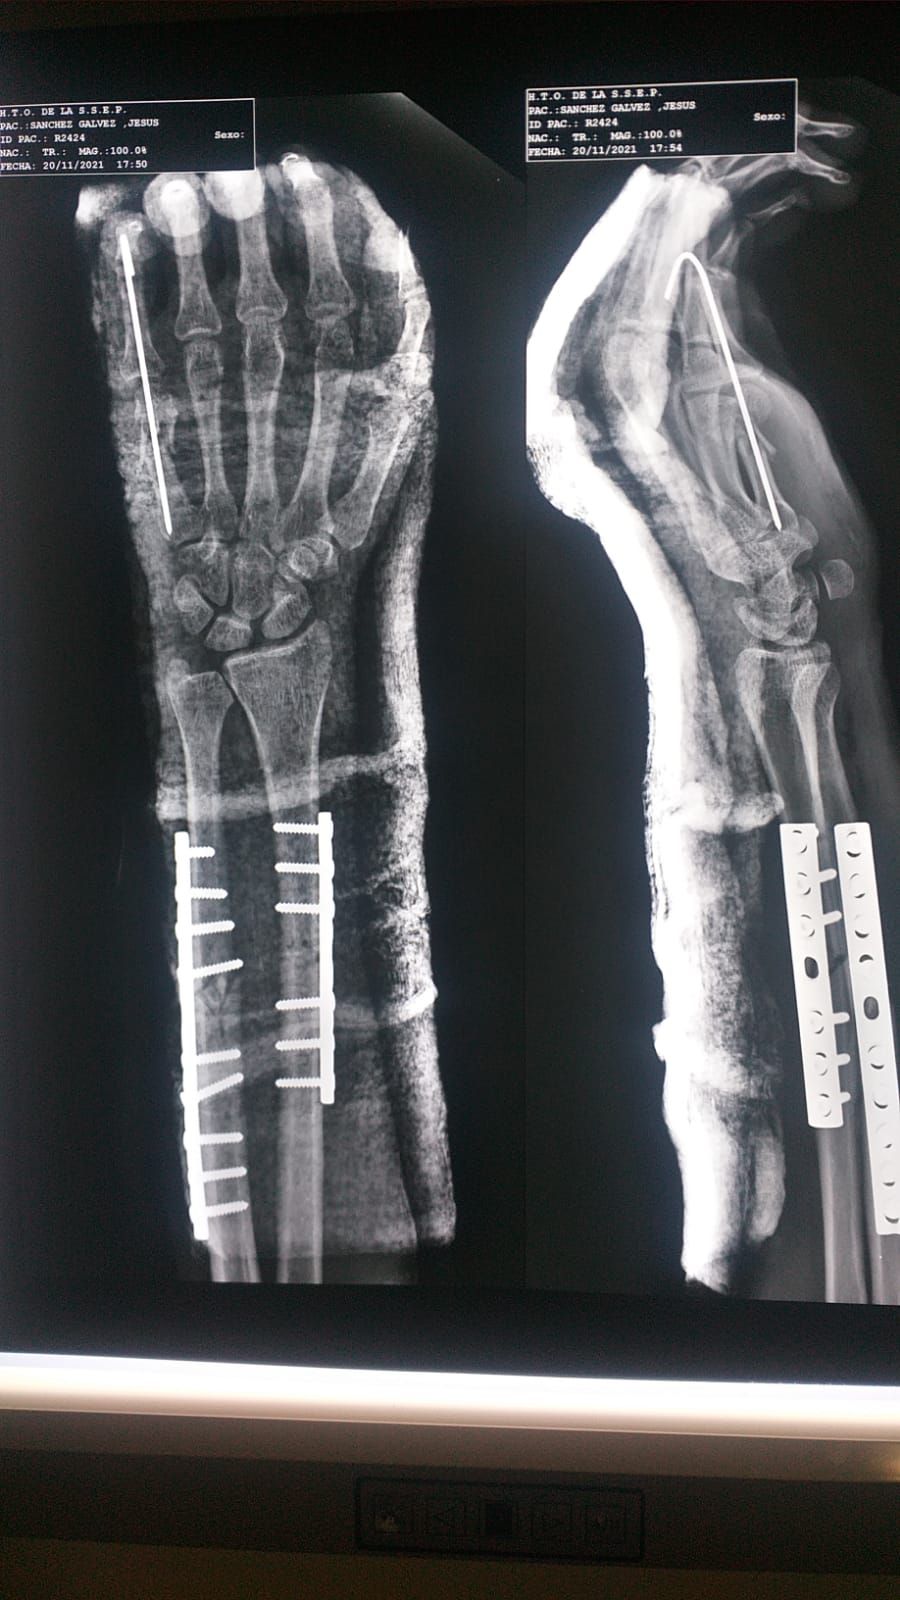

• Fractura de antebrazo

• Fractura de mano

Reparación de fracturas de cúbito y radio Sin especificar